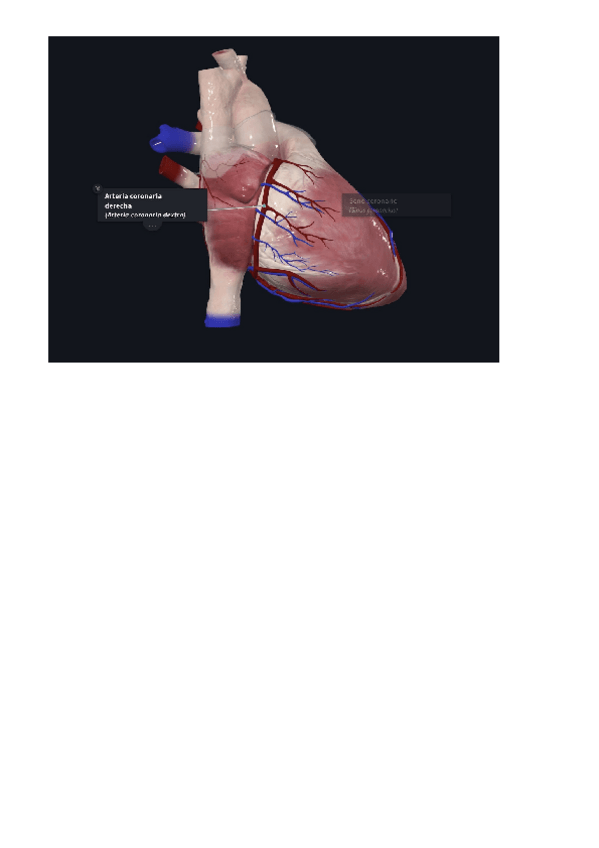

Practica-1-lab-Anatomia.pdf